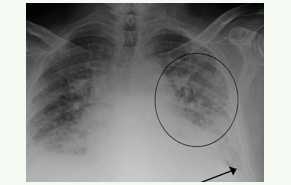

2

4

CXR - bilateral pul infiltrates